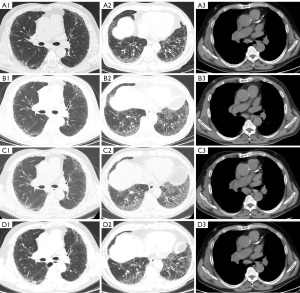

In April 2018, a 56-year-old male came to our hospital with the main complaint of recurrent cough and dyspnea on exertion, with no immunological features [including antinuclear antibody (ANA) profile, anti-neutrophil cytoplasmic antibody (ANCA) profile and etc.] but 40-year smoking history. Physical examination revealed bibasilar crackles. The patient’s immunological indicators, including ANA and ANCA, were all negative. Pulmonary function tests indicated reduced lung capacity [total lung capacity (TLC) at 69.6% of predicted value] and decreased diffusion function [diffusing capacity of the lung for carbon monoxide (DLCO) at 62.4% of predicted value]. As shown in Figure 1, high-resolution chest computed tomography (HRCT) (Figure 1, A1-A3) showed subpleural reticular opacities predominantly in the lower lobes, with some honeycombing changes, consistent with UIP. Pathological examination of a transbronchial lung biopsy from the right lower lobe revealed chronic inflammation and fibrous tissue proliferation. The patient was diagnosed as fILD, with a high possibility of IPF. Due to personal concerns, the patient refused antifibrotic medication. After 4 weeks of oral prednisone, there was no significant improvement in symptoms, and the patient discontinued the medication. However, pulmonary function tests indicated a further decline in DLCO (50.5% of predicted value), and the patient agreed to start pirfenidone, the only available anti-fibrotic choice at that time, but discontinued it after 1 month due to poor tolerance to gastrointestinal adverse events (especially nausea, abdominal distension and anorexia). In January 2021, a chest CT revealed a suspicious small nodule in the posterior basal segment of the right lower lobe and exacerbated fibrosis (Figure 1, B1-B3), with stable clinical symptoms. In January 2022, further laboratory tests revealed that the vital tumor markers [including carcinoembryonic antigen (CEA), neuron-specific enolase (NSE) and Cyfra211] were all within normal range, and chest HRCT showed progression of pulmonary fibrosis predominantly near the pleura in both lower lungs, with a new small nodule in the right lower lung and some enlargement of the hilar and mediastinal regions (Figure 1, C1-C3). Further endobronchial ultrasound-guided transbronchial needle aspiration (EBUS-TBNA) of the 7th group of lymph nodes revealed clusters of atypical cells in the inflammatory exudate, consistent with malignancy, shown in Figure 2. Immunohistochemistry results showed CK7 (+), TTF-1 (+), ALK-D5F3 (−), P40 (−), ALK-D5F3 (NC) (−). Tumor molecular pathology testing indicated EGFR 19del (+) 5.2%, diagnosing NSCLC stage IIIB (EGFR exon 19 deletion). After a thorough discussion with clinicians of lung cancer and interstitial lung disease, the patient agreed to continue treatment with pirfenidone 600 mg tid and icotinib 125 mg tid on March 3, 2022. In this time, we adopted a dose titration strategy for pirfenidone, under which the patients achieved satisfactory tolerance. The chest CT in June showed that the right lung nodule size reduced from 1.0 to 0.6 cm, with no significant change in lymph node size or degree of pulmonary fibrosis (Figure 1, D1-D3), and the treatment was evaluated as partial remission (PR), defined as at least a 30% decrease in the sum of diameters of target lesions, taking as reference the baseline sum diameters. On December 4, 2022, the patient was tested positive for coronavirus disease 2019 (COVID-19) and passed away due to severe COVID-19 pneumonia and respiratory failure on Dec 22, 2022. The chest HRCT confirmed COVID-19 pneumonia was shown in Figure S1. The timeline of the patient’s history is shown in Table 1.